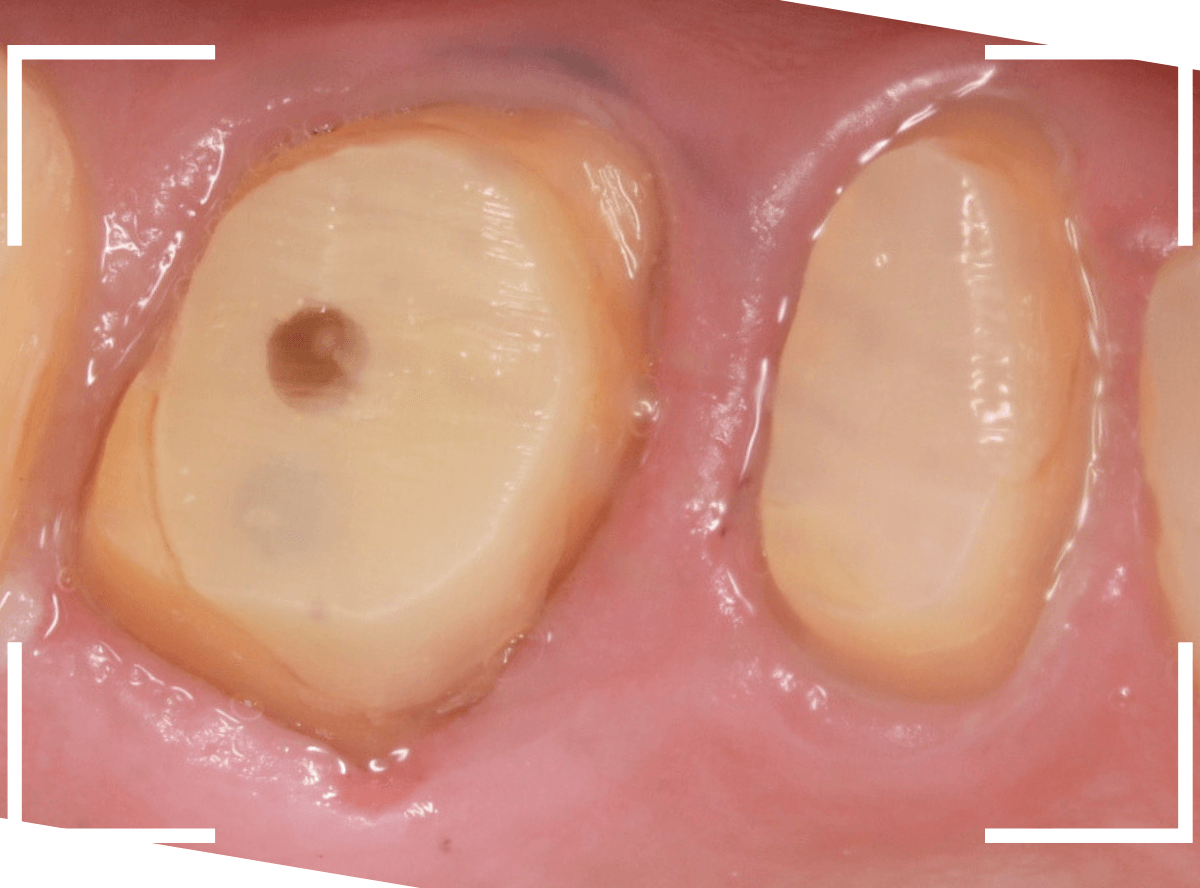

さし歯の土台の補修と、おやしらずの虫歯の処置をしたところです。

この状態で型をとります。